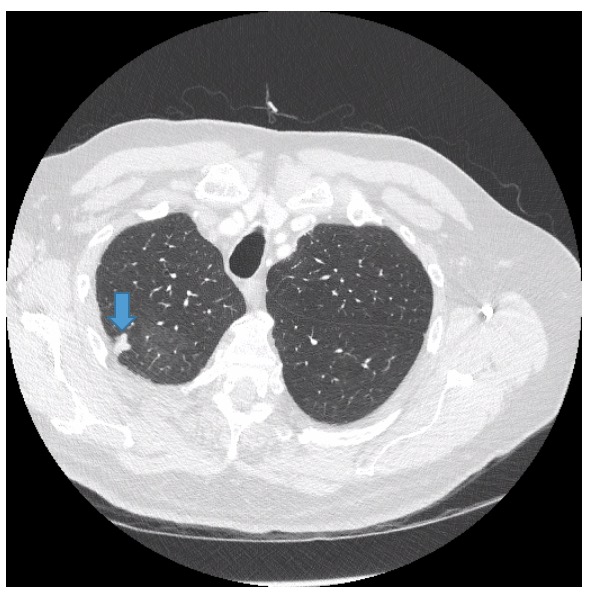

Diagnostic tests. Routine colonoscopy findings of the descending colon were unremarkable; however, the colonoscope could not be advanced in the transverse colon to the hepatic flexure. Consequently, CT colonography without contrast, more popularly referred to as virtual colonoscopy, was performed, the results of which showed eventration of the left hemidiaphragm with a large hiatal hernia containing transverse colon (Figure 1), as well as incidentally noted ill-defined nodular opacities within the right upper lobe with concomitant ground-glass attenuation (Figure 2).

Figure 2. Also noted incidentally on virtual CT were ill-defined nodular opacities within the right upper lobe with concomitant ground-glass attenuation.

Contrast-enhanced chest CT scans showed a 1-cm nodular opacity (Figure 4) and a 1.6-cm subpleural nodular opacity (Figure 5) within the apical segment of the right upper lobe, and ill-defined ground-glass opacity within the posterior segment of the right upper lobe (Figure 6).

Figure 4. Contrast-enhanced chest CT showed a 1-cm nodular opacity in the apical segment of the right upper lobe.

Figure 5. Contrast-enhanced chest CT showed a 1.6-cm subpleural nodular opacity within the apical segment of the right upper lobe.

Figure 6. Contrast-enhanced chest CT showed ill-defined ground-glass opacity within the posterior segment of the right upper lobe.

The impression was right upper lobe nodular opacities for which 3-month follow-up would be recommended.